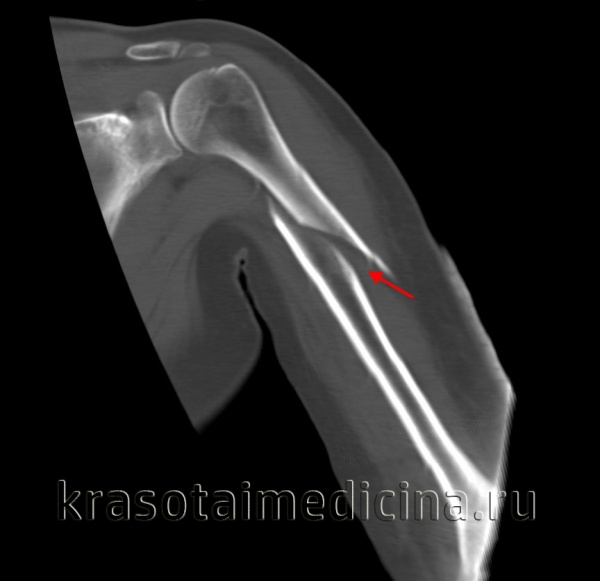

КТ плечевого сустава. Оскольчатый перелом хирургической шейки плечевой кости со смещением отломков. Дистальный отломок (красная стрелка) вколочен в проксимальный отломок (синяя стрелка).

(Справа) На боковой рентгенограмме у этою же пациента определяется передне-задняя ротация на 90° суставной поверхности головки мыщелка плечевой кости. Обратите внимание на приподнятые околосуставные жировые подушки, указывающие на гемартроз в результате острой травмы. (Слева) На сагиттальной 2D КТ с реформатированием определяется оскольчатый перелом головки мыщелка плечевой кости со смещением. Основной отломок часто смещается кпереди и может быть сильно ротирован. Кроме того, имеется перелом венечною и локтевого отростков.

(Справа) На осевой КТ у этого же пациента определяется фронтально ориентированный перелом юловки мыщелка плечевой кости, переходящий медиально на блок. По классификации Брайена и Моррея переход перелома на блок соответствует 4 типу повреждения.